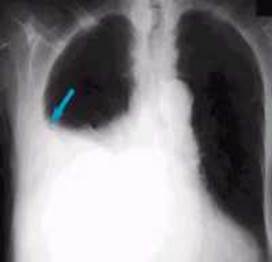

Женщина 63 года. На рентгенограммах органов грудной клетки отмечается ровная, светлая (2 мм) линия в переднем отрезке 5-го ребра слева, линия поперечно пересекает ребро, проксимальные и дистальные отрезки ребра до линии находятся на одном уровне (смешение до 3 мм). Жалуется на боли и затруднение дыхания, особой травмы не было, «перетрудилась» на даче. Данные изменения наиболее характерны для:

A) Лоозеровской зоны перестройки

B) Перелома ребра

C) Наслоения сосудистого рисунка легкого

D) Артефакта

E) Спонтанного пневмоторакса

{Правильный ответ}= B